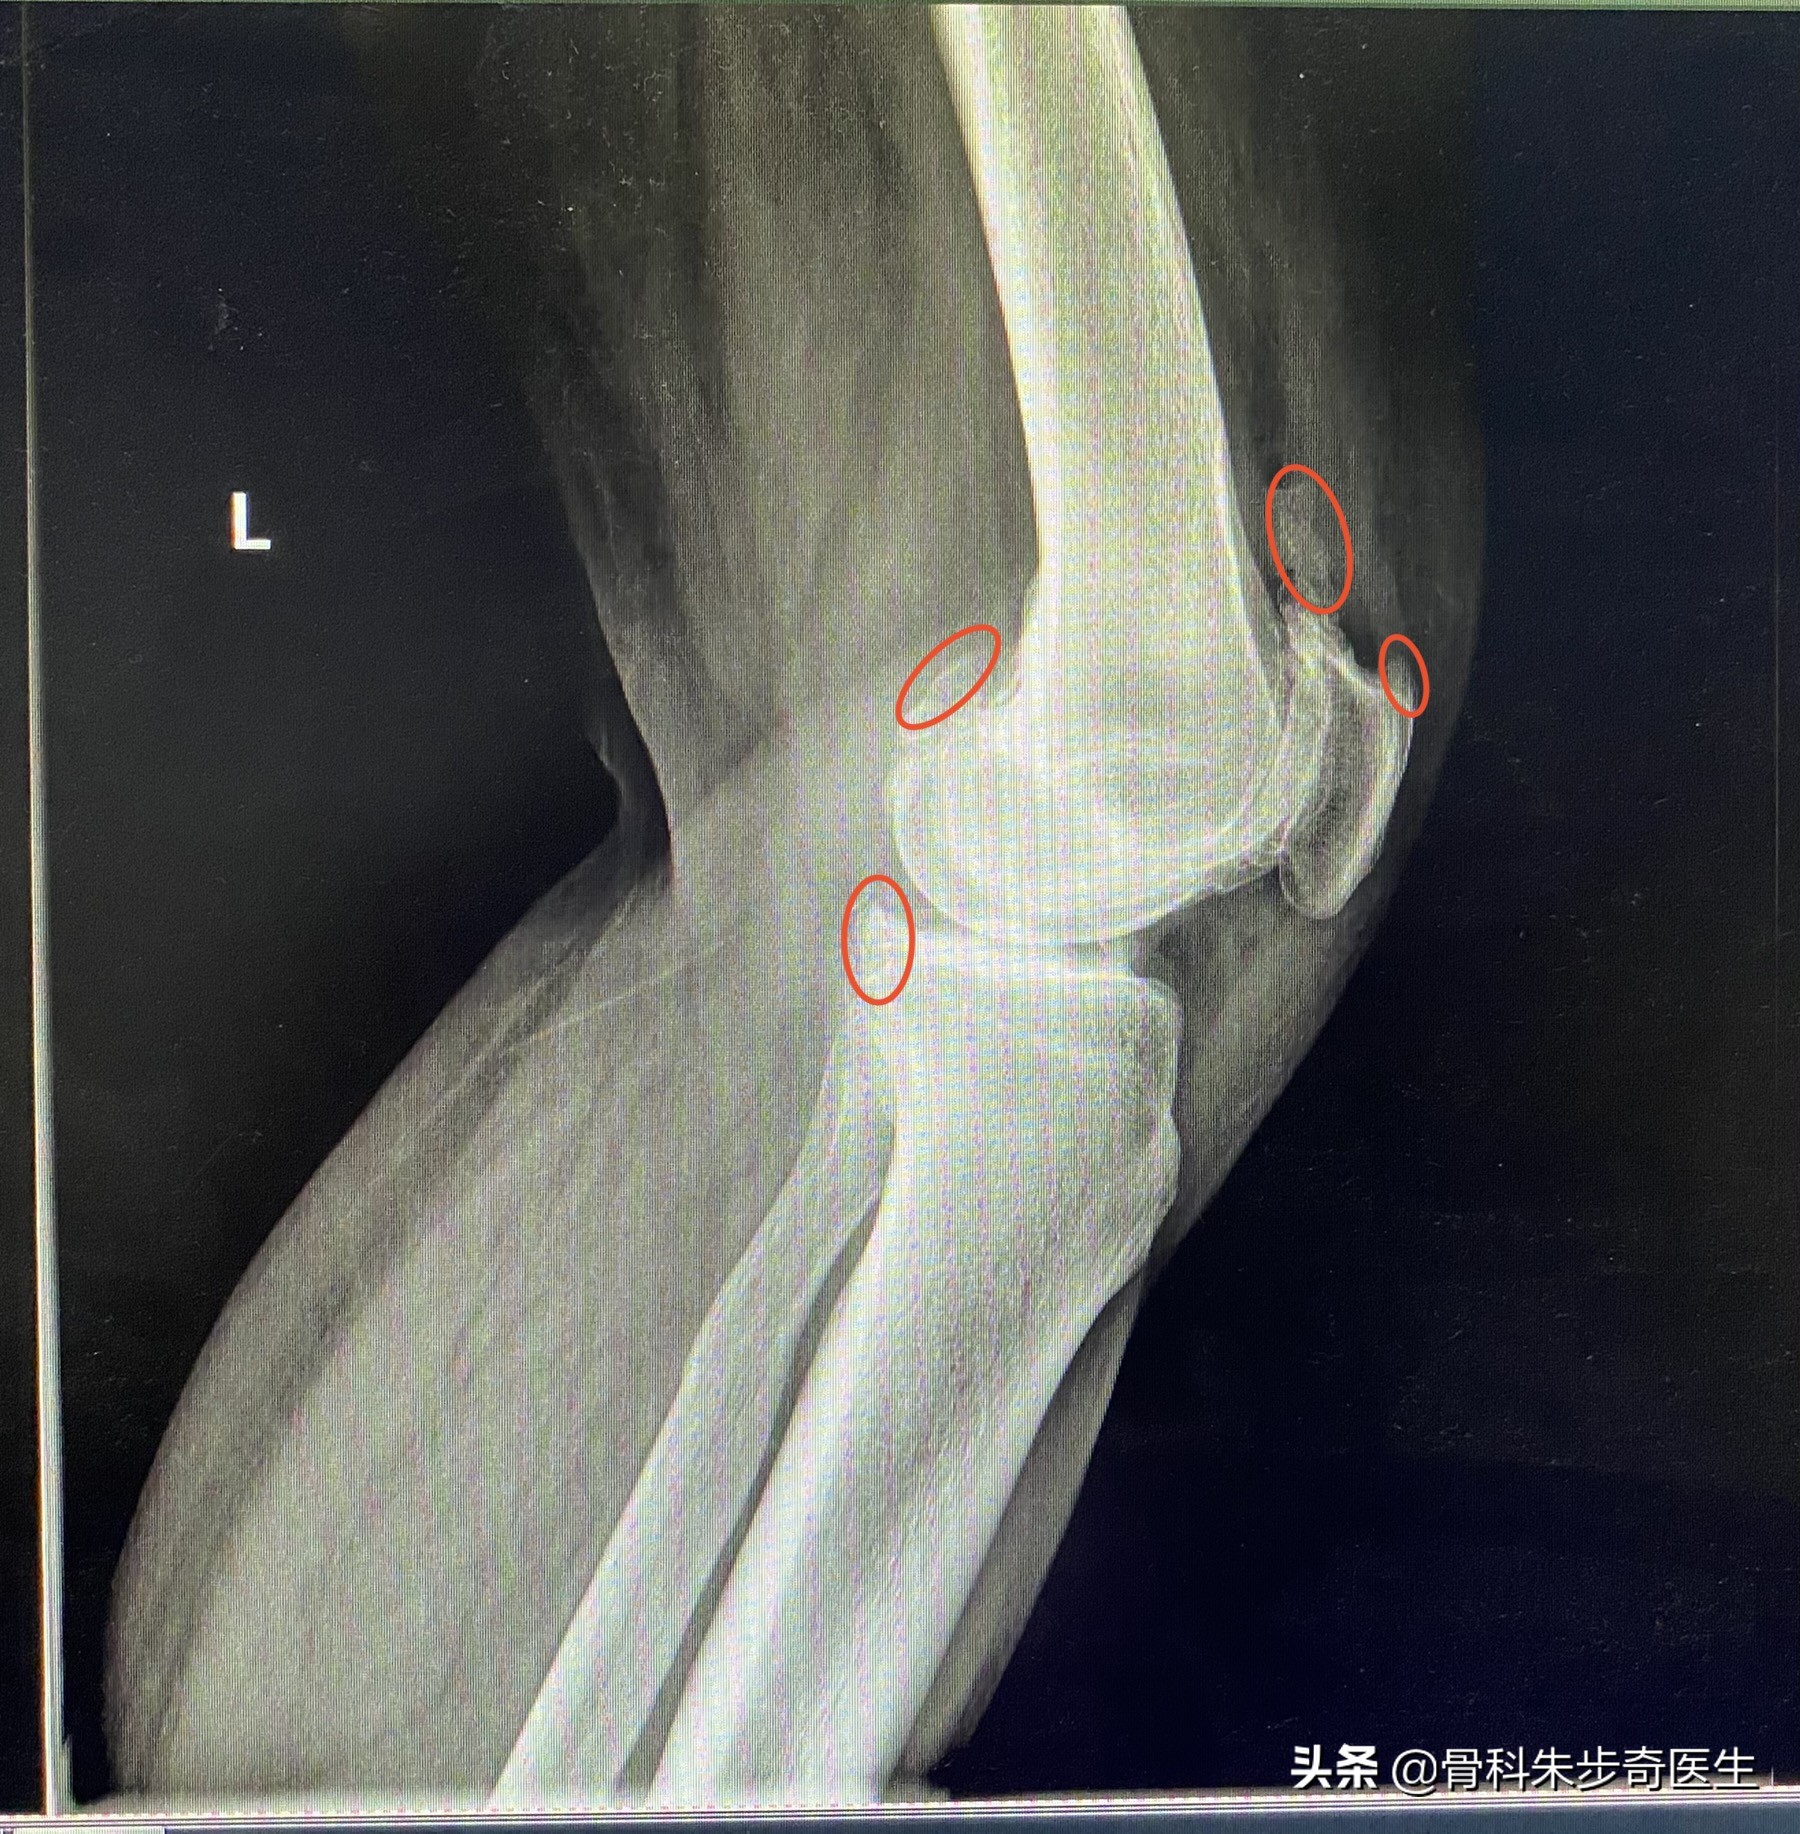

先不看片子,先检查一下膝关节:首先能够发现,膝关节有点肿胀,查了一下,髌骨上方的关节囊确实有积液,同时,髌骨下方的关节面也有退变,半月板也有问题,于是看了下片子:

从片子上可以看出来,这些红色标记的地方都是骨质增生,也就是我们说的骨刺,但是骨刺本身并不是什么问题,我曾经反复强调过,骨刺本省不会引起任何症状,引起症状的是内部的软骨退变,游离体,半月板损伤,这些才是因,骨刺最后只是结果而已。

但是因为她的膝关节肿胀,关节内部还有游离体,说明内部关节退变比较严重,这个时候给她解释道,您这个关节不只只是骨刺的问题,更多的是关节内部的软骨有退变了,而且还有游离体,这个游离体得取出来,不取的话会把关节搞坏了,所以还是建议住院做个小手术,把游离体取出来,顺便清理一下关节。